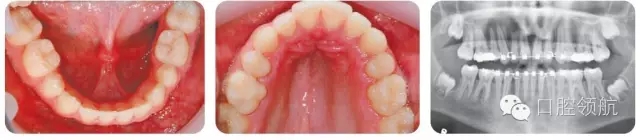

圖3.16展示了患者治療結(jié)束時(shí)的口內(nèi)像和面像,其糾正后牙反的療效穩(wěn)定嗎?

擴(kuò)弓治療存在不穩(wěn)定性。長(zhǎng)期的隨訪調(diào)查顯示,擴(kuò)弓治療結(jié)束后,不論是牙弓或者牙槽骨都存在顯著的縮窄。因此,擴(kuò)弓治療結(jié)束后需要長(zhǎng)期保持,這里推薦使用Hawley式保持器。與此同時(shí),拔除下頜第二前磨牙以及下牙弓的縮窄相對(duì)而言更加穩(wěn)定,因此有助于反糾正療效穩(wěn)定性的提高。